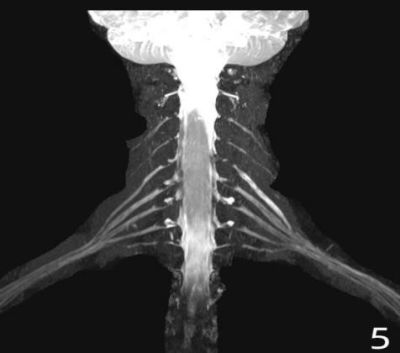

Figure1. Axial CT scanning, locating the upper edge of the facet joint process as the puncture target; After puncture along the predetermined route, inject 10ml ozone; 10ml normal saline and 1ml contrast agent were injected again to show the distribution of contrast agent; After operation, ozone was well distributed in the spinal canal and around the spinal nerve root.